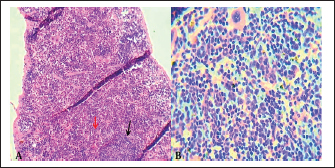

The normal histological view of the spleen sections showed a normal lymphoid follicles and normal splenic sinusoidal red pulp with normal population of megakaryocytes (Fig. 9), compared with the histopathological figures of the infected spleen that showed marked atrophy of lymphoid follicles with multiple focal cellular depletion and mild congestion of splenic sinusoid and focal hemorrhage with presence of fibrin thrombi (Fig. 10), other figures showed sub capsular degeneration of lymphoid tissue with infiltration of leukocytes. The magnification of these figures of spleen shows chlamydial inclusion bodies of C. psttaci within the cytoplasm of macrophages (Fig. 11).

Fig. 9. A). Section of spleen (control) shows: normal lymphoid follicles (black arrow) and normal splenic sinusoidal red pulp (red arrow). H&E stain.100x. B). Section of spleen (control) shows: normal lymphoid follicles and normal splenic sinusoid with normal population of megakaryocytes and splenic cords. H&E stain.400x.

Fig. 10. A). Section of chlamydial-infected spleen shows: atrophy of lymphoid follicles with multiple focal cellular depletion (red arrows) and congestion with distention of splenic sinusoid (black arrow) and focal hemorrhage (yellow arrow). H&E stain 100x. B). Section of spleen (infected) shows chlamydial inclusion bodies (IB) within the cytoplasm of macrophages (black arrows). H&E stain 400x.

Fig. 11. A). Section of spleen (infected) shows subcapsular degeneration of lymphoid tissue with infiltration of leukocytes and chlamydial inclusion bodies (Red arrow). H&E stain 400x. B). Individual chlamydial inclusion bodies (IB) of C. psittaci stained purple within the cytoplasm of macrophages (Black arrow). Giemsa stain 400x.